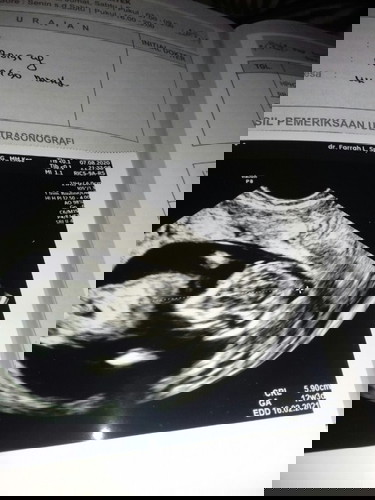

Sedih sih rasanya di tes positip di usg juga ada, tapi knapa keluaran darah tiap pagi😭kata dok debay nya shat.. Tapi wktu itu saya gx hed 1thn sesudh di lepas kb yg 3bln sekali,udh msuk 2thn aq lepas terus aq minum fil 3bln krna aq pingin hed nya lancar..terus disitu udh stop hed smpai skrng aq sllu tes tiap bln hasilnya negatip, terus bagian bln juni aq tes karna aq sakit hasil ny postip,terus begitu aq periksa ke bidan,kata bidan di usg aj soalnya blm tau hpl nya,soalny gx terakhir hed nya.. terus wktu itu aq kena pendarahan kaya kegguran, terus aq usg 4D soalnya pingin keliatan gitu apakah ada janin apakah engga. Pas usg janin ada udh masuk 13week, kata dok debay nya shat cuma ada pendarahan doang, dok saran jangan hb sama jgn aktipitas dlu soalnya kndungan ku lemah😭mau tanya ini pendarahan darh yg 1thn apa gimna aq sedih sih#Nanya #jangandibully ank yg ke 3

Minggu kemrin sya pendarahan, tapi alhamdulillah di usg bayi nya sehat